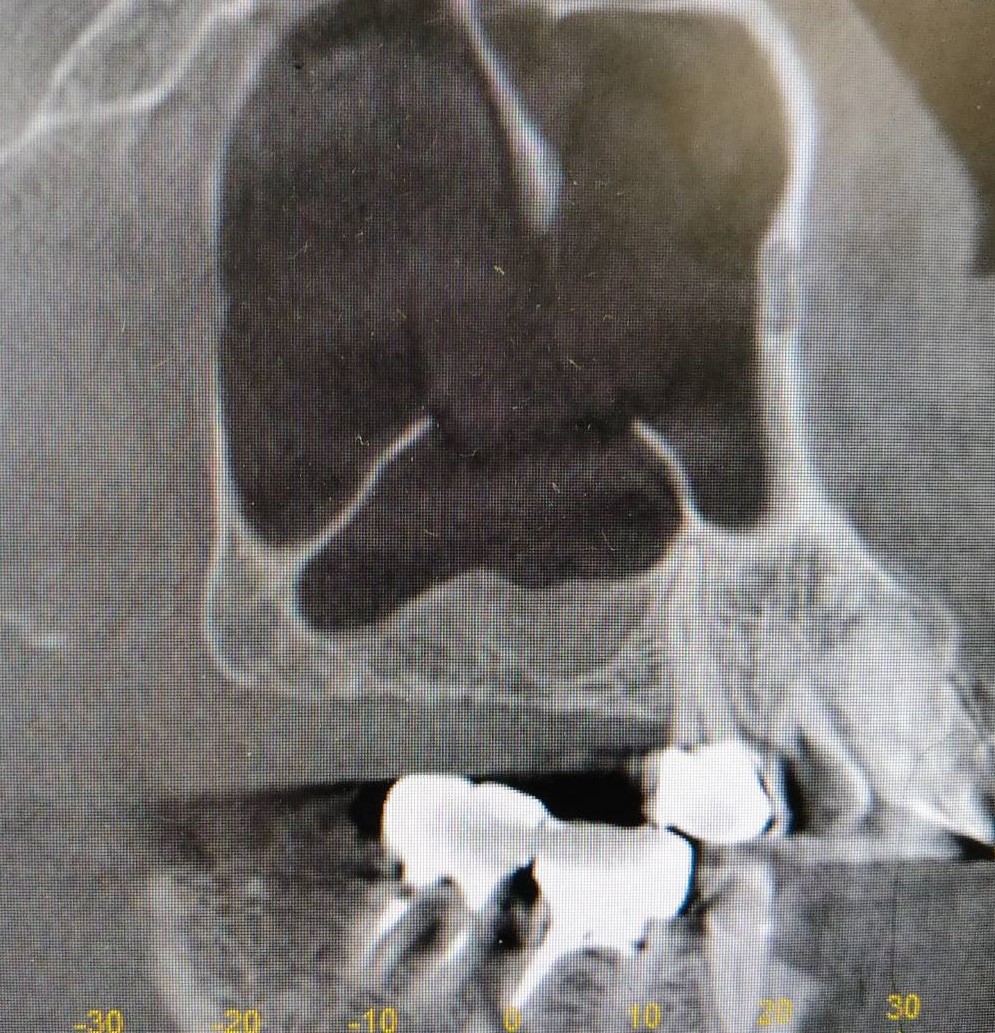

上顎洞底挙上術を併用したインプラント埋入の症例紹介

Before

After

6か月後

インプラント埋入

主訴

右上奥歯にインプラントを入れたい。

治療内容

右上奥歯の骨が薄いため、まず人工骨を用いて造骨しました。6か月後に骨ができたのでインプラントを埋入しました。

治療費

上顎洞底挙上術:165,000円(税込)

インプラント埋入術:220,000円(税込)

治療期間

7か月

通院回数

5回

想定されたリスク

※上顎洞粘膜穿孔、上顎洞炎、腫脹、内出血、鼻出血の可能性がありました。

石毛 俊作先生

大神宮デンタルクリニック

インプラントを埋入する際に十分な骨量がない場合は骨造成を行います。骨造成の方法は症例によって異なりますが、今回のケースは上顎洞底挙上術を用いました。